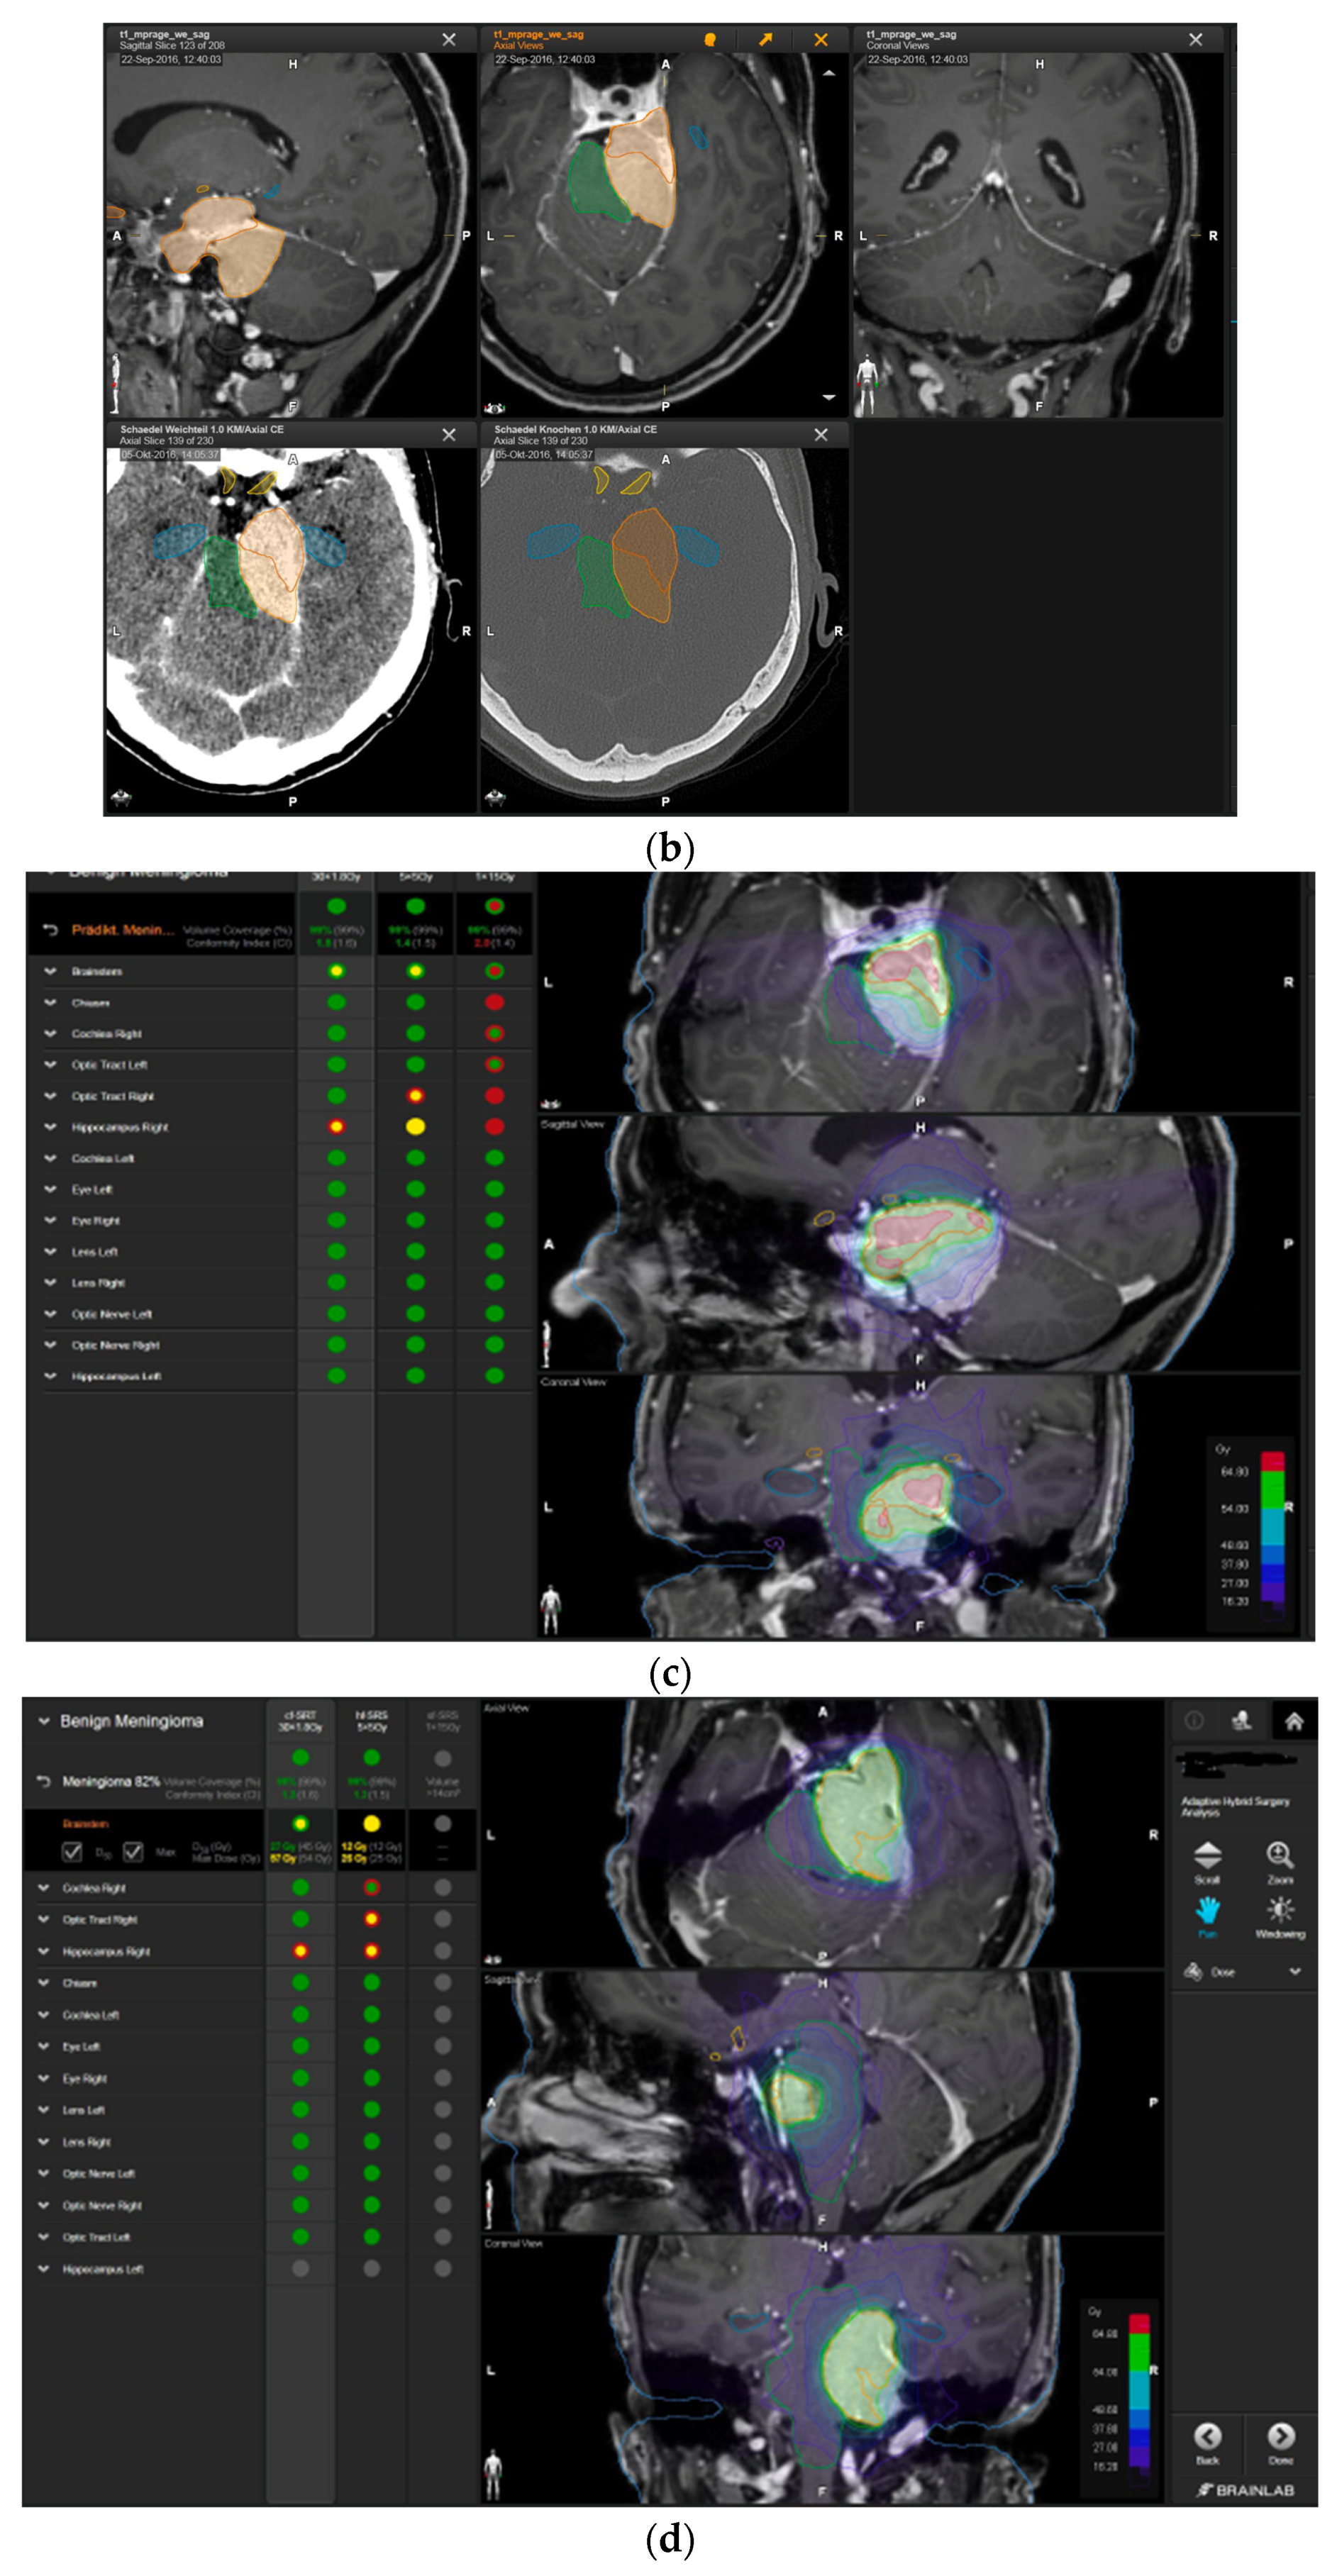

Figure 3.

First representative case with AHSA-assisted tumor resection. (a) Preoperative MRI imaging of tumor (orange) and planned residual tumor volume (red). (b) Dose constraints in the AHSA software for conventional, hypofractionated radiotherapy, and radiosurgery planning for the preoperatively defined residual tumor volume. With this plan, conventional fractionated and hypofractionated radiotherapy were feasible, with effective tumor coverage.

—brainstem: max. dose is marginally safe, whereas mean dose is safe. For single fraction stereotactic radiosurgery, the tumor volume coverage seems effective, while the conformity index was indicating over-treatment.

—brainstem: mean dose is safe, while max. dose is unsafe;

—chiasm: mean dose is unsafe, while max. dose is safe;

—right optic tract: mean dose is unsafe, while max. dose is safe. (c) First intraoperative structure update (ISU) at the time point of 65% residual tumor volume, showing the tumor coverage and organ at risk constraints. At this stage of the resection, AHSA demonstrated that only conventional and hypofractionated radiotherapy were feasible.

—brainstem: max. dose is marginally safe, whereas mean dose is safe. (d) Second ISU acquisition and residual tumor reduction to 58%. (e) Third ISU acquisition with a reduction of residual tumor volume to 41%. Dose constraints for conventional, hypofractionated radiotherapy, and radiosurgery are demonstrated. At the final stage of the resection, the conventional and hypofractionated radiotherapy organ risk constraints were unchanged.

—brainstem shows that max. dose is marginally safe, whereas mean dose is safe. The single-dose stereotactic radiosurgery constraints show that:

—brainstem: mean dose safe, max. dose unsafe;

—chiasm: mean dose unsafe, max. dose safe;

—right optic tract: mean dose marginally safe, max. dose unsafe. (f) Fusion of intraoperative CT to final intraoperative ISU. (g) Preoperative and 3 months postoperative MRI imaging for planning of radiosurgery (5 × 5 Gy).